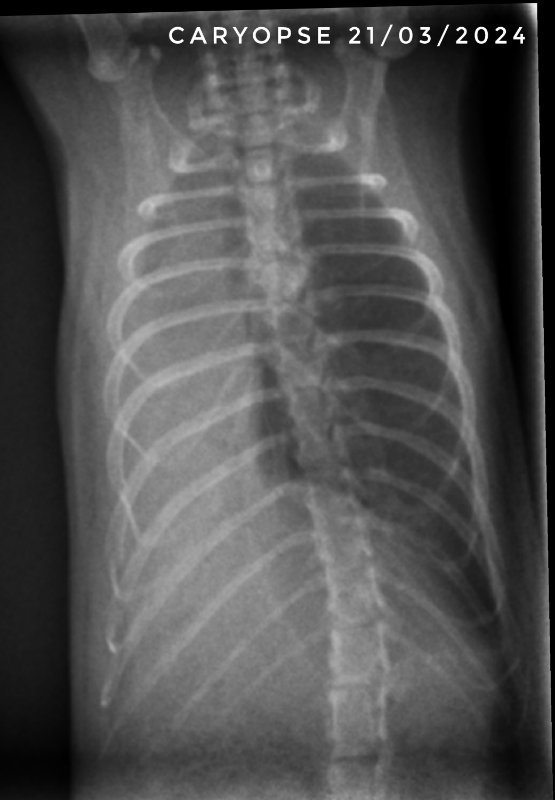

Et voici les dernières radios de Drupe. On est donc normalement sereins, les poumons ne sont pas parfaits, mais on est sûrement sur des cicatrices. Maintenant, il lui reste à passer l'étape de la castration et normalement ensuite il sera tranquille niveau soins vetos ^^

Le seul ayant eu du chloramphénicol est décédé. Pour les autres c'est le trio tylosine par nébu + doxycycline et azythromycine qui a été efficace. Après les filles ont eu très peu de symptômes (la plus touchée c'était ma petite Graine, que j'ai gardée donc, et qui n'a jamais eu les poumons touchés pour autant).